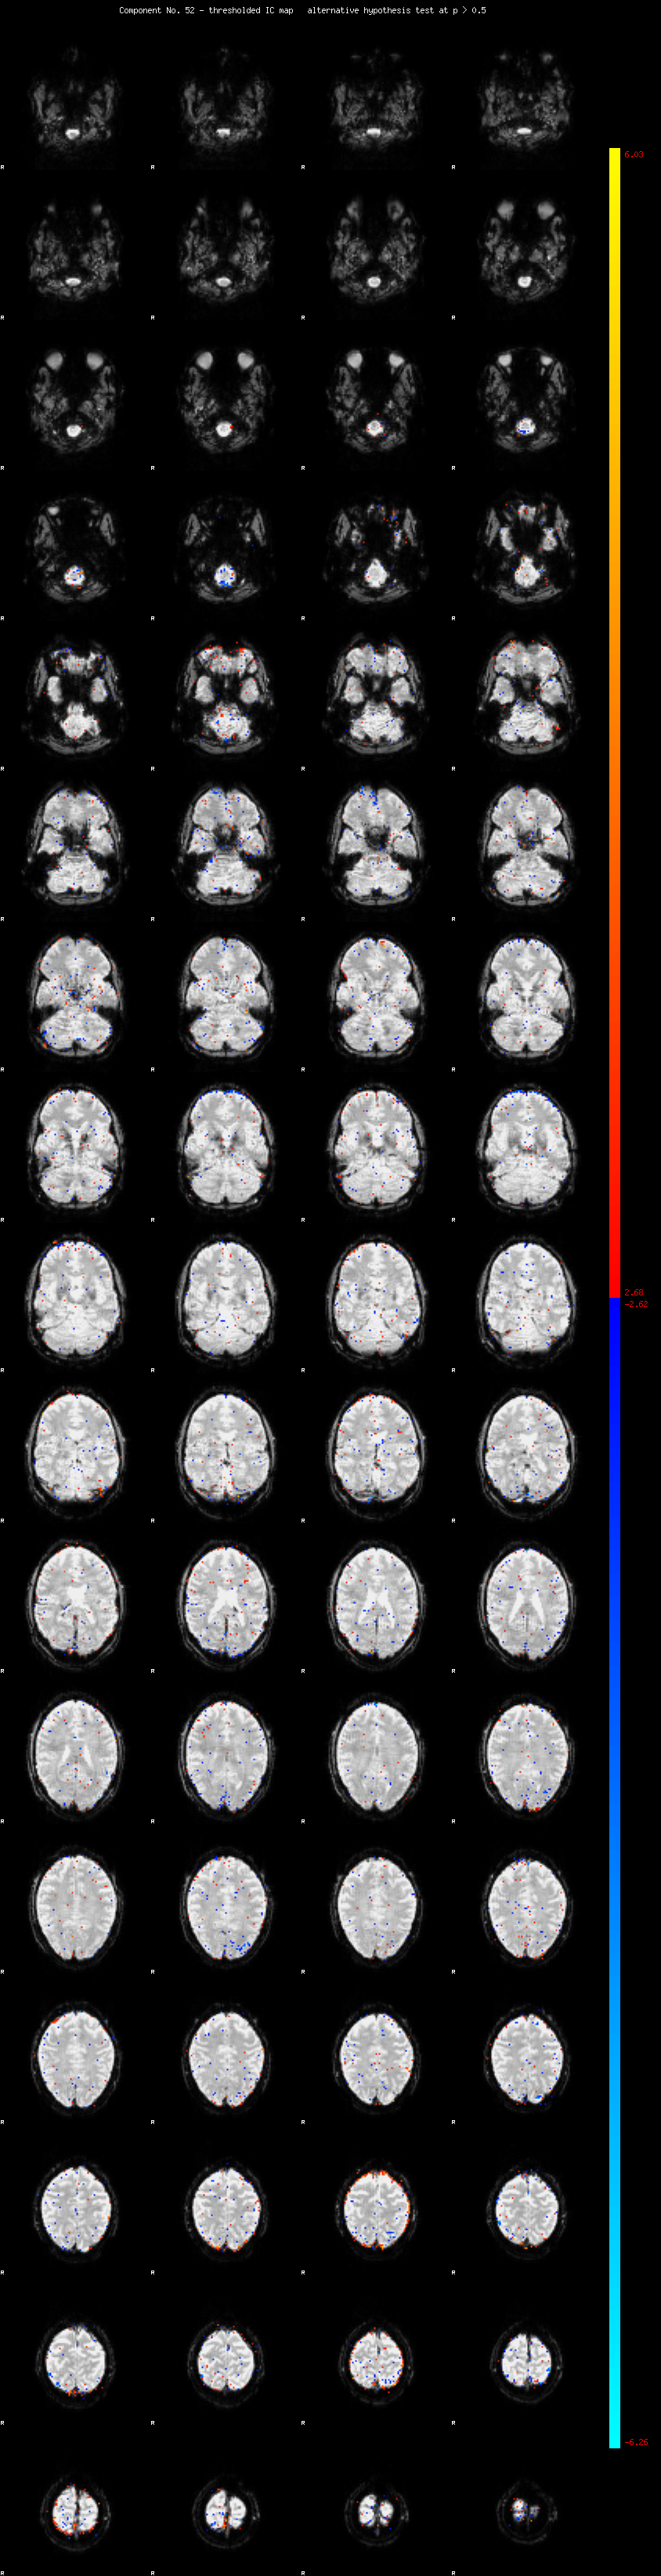

MELODIC Component 52

0.93 % of explained variance;     0.62 % of total variance

MMfit